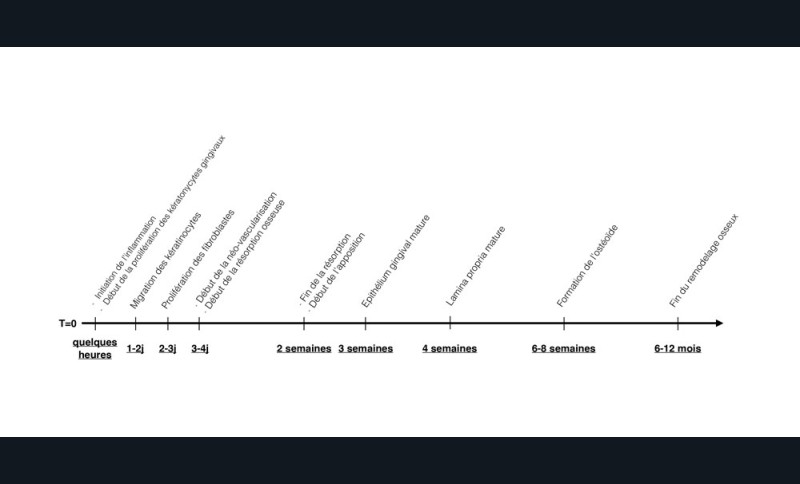

La cicatrisation est le résultat d’une succession coordonnée d’événements, impliquant la migration, la prolifération et l’expression phénotypique d’un grand nombre de types cellulaires. Elle permet le dépôt et le remodelage d’une matrice extra-cellulaire spécifique du tissu lésé, et se divise classiquement en 3 étapes :

•l’inflammation, étroitement liée au processus d’hémostase, permet la détersion de la plaie et aboutit à la formation d’une matrice spécifique qui sera le support de la phase de prolifération,

• la prolifération, caractérisée par la formation d’un tissu de granulation qui remplace progressivement le caillot de fibrine. Elle s’accompagne de la ré-épithélialisation de la plaie,

• la consolidation, correspond à un remodelage qui se poursuit pendant plusieurs mois, permet une adaptation fonctionnelle du tissu (fig. 1).